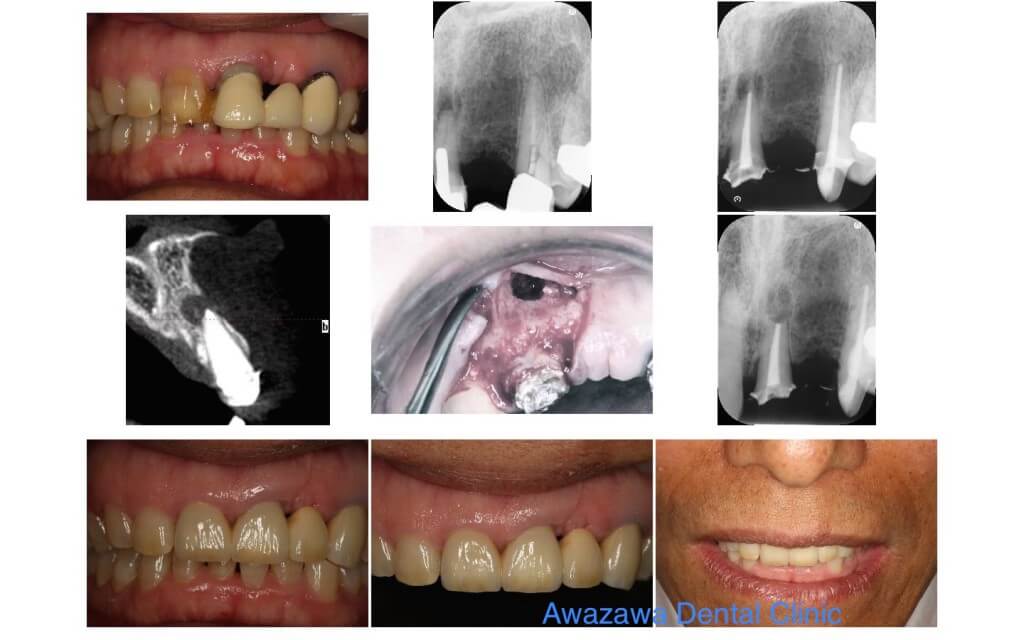

Case.4

処置された前歯の根の先に大きな嚢胞の陰が認められます。根の再処置を施した後に感染した部分の切断を行い嚢胞と共に摘出した症例です。 歯肉の安定した後にセラミッククラウンによる補綴処置を行いました。

Case.6

不適合な補綴処置がなされ、根の部分には器具の破折による病変が認められます。根の再処置を行った後に根先端部の削除を行い病変を除去した症例です。 再補綴処置を施し審美的に処置いたしました。